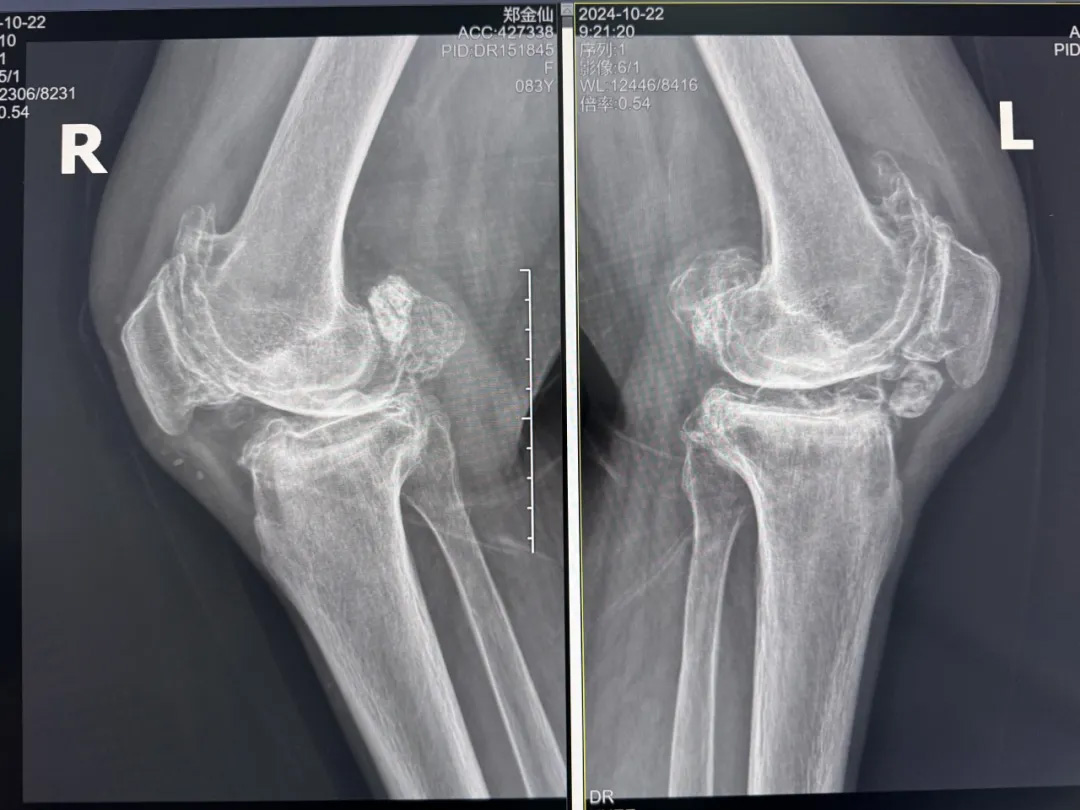

年輕時(shí)愛到處走走的鄭阿婆,晚年卻被雙膝劇痛困在輪椅上長(zhǎng)達(dá)二十年。經(jīng)羅副院長(zhǎng)診斷,她的膝關(guān)節(jié)軟骨幾乎磨光,關(guān)節(jié)嚴(yán)重畸形,呈"羅圈腿",走幾步便疼痛鉆心,連如廁都需家人抱扶。“我這輩子啊,估計(jì)再也站不起來了。”是阿婆最常說的話。

在家人幾乎放棄希望時(shí),AI三維規(guī)劃技術(shù)為這場(chǎng)"關(guān)節(jié)保衛(wèi)戰(zhàn)"帶來轉(zhuǎn)機(jī)。